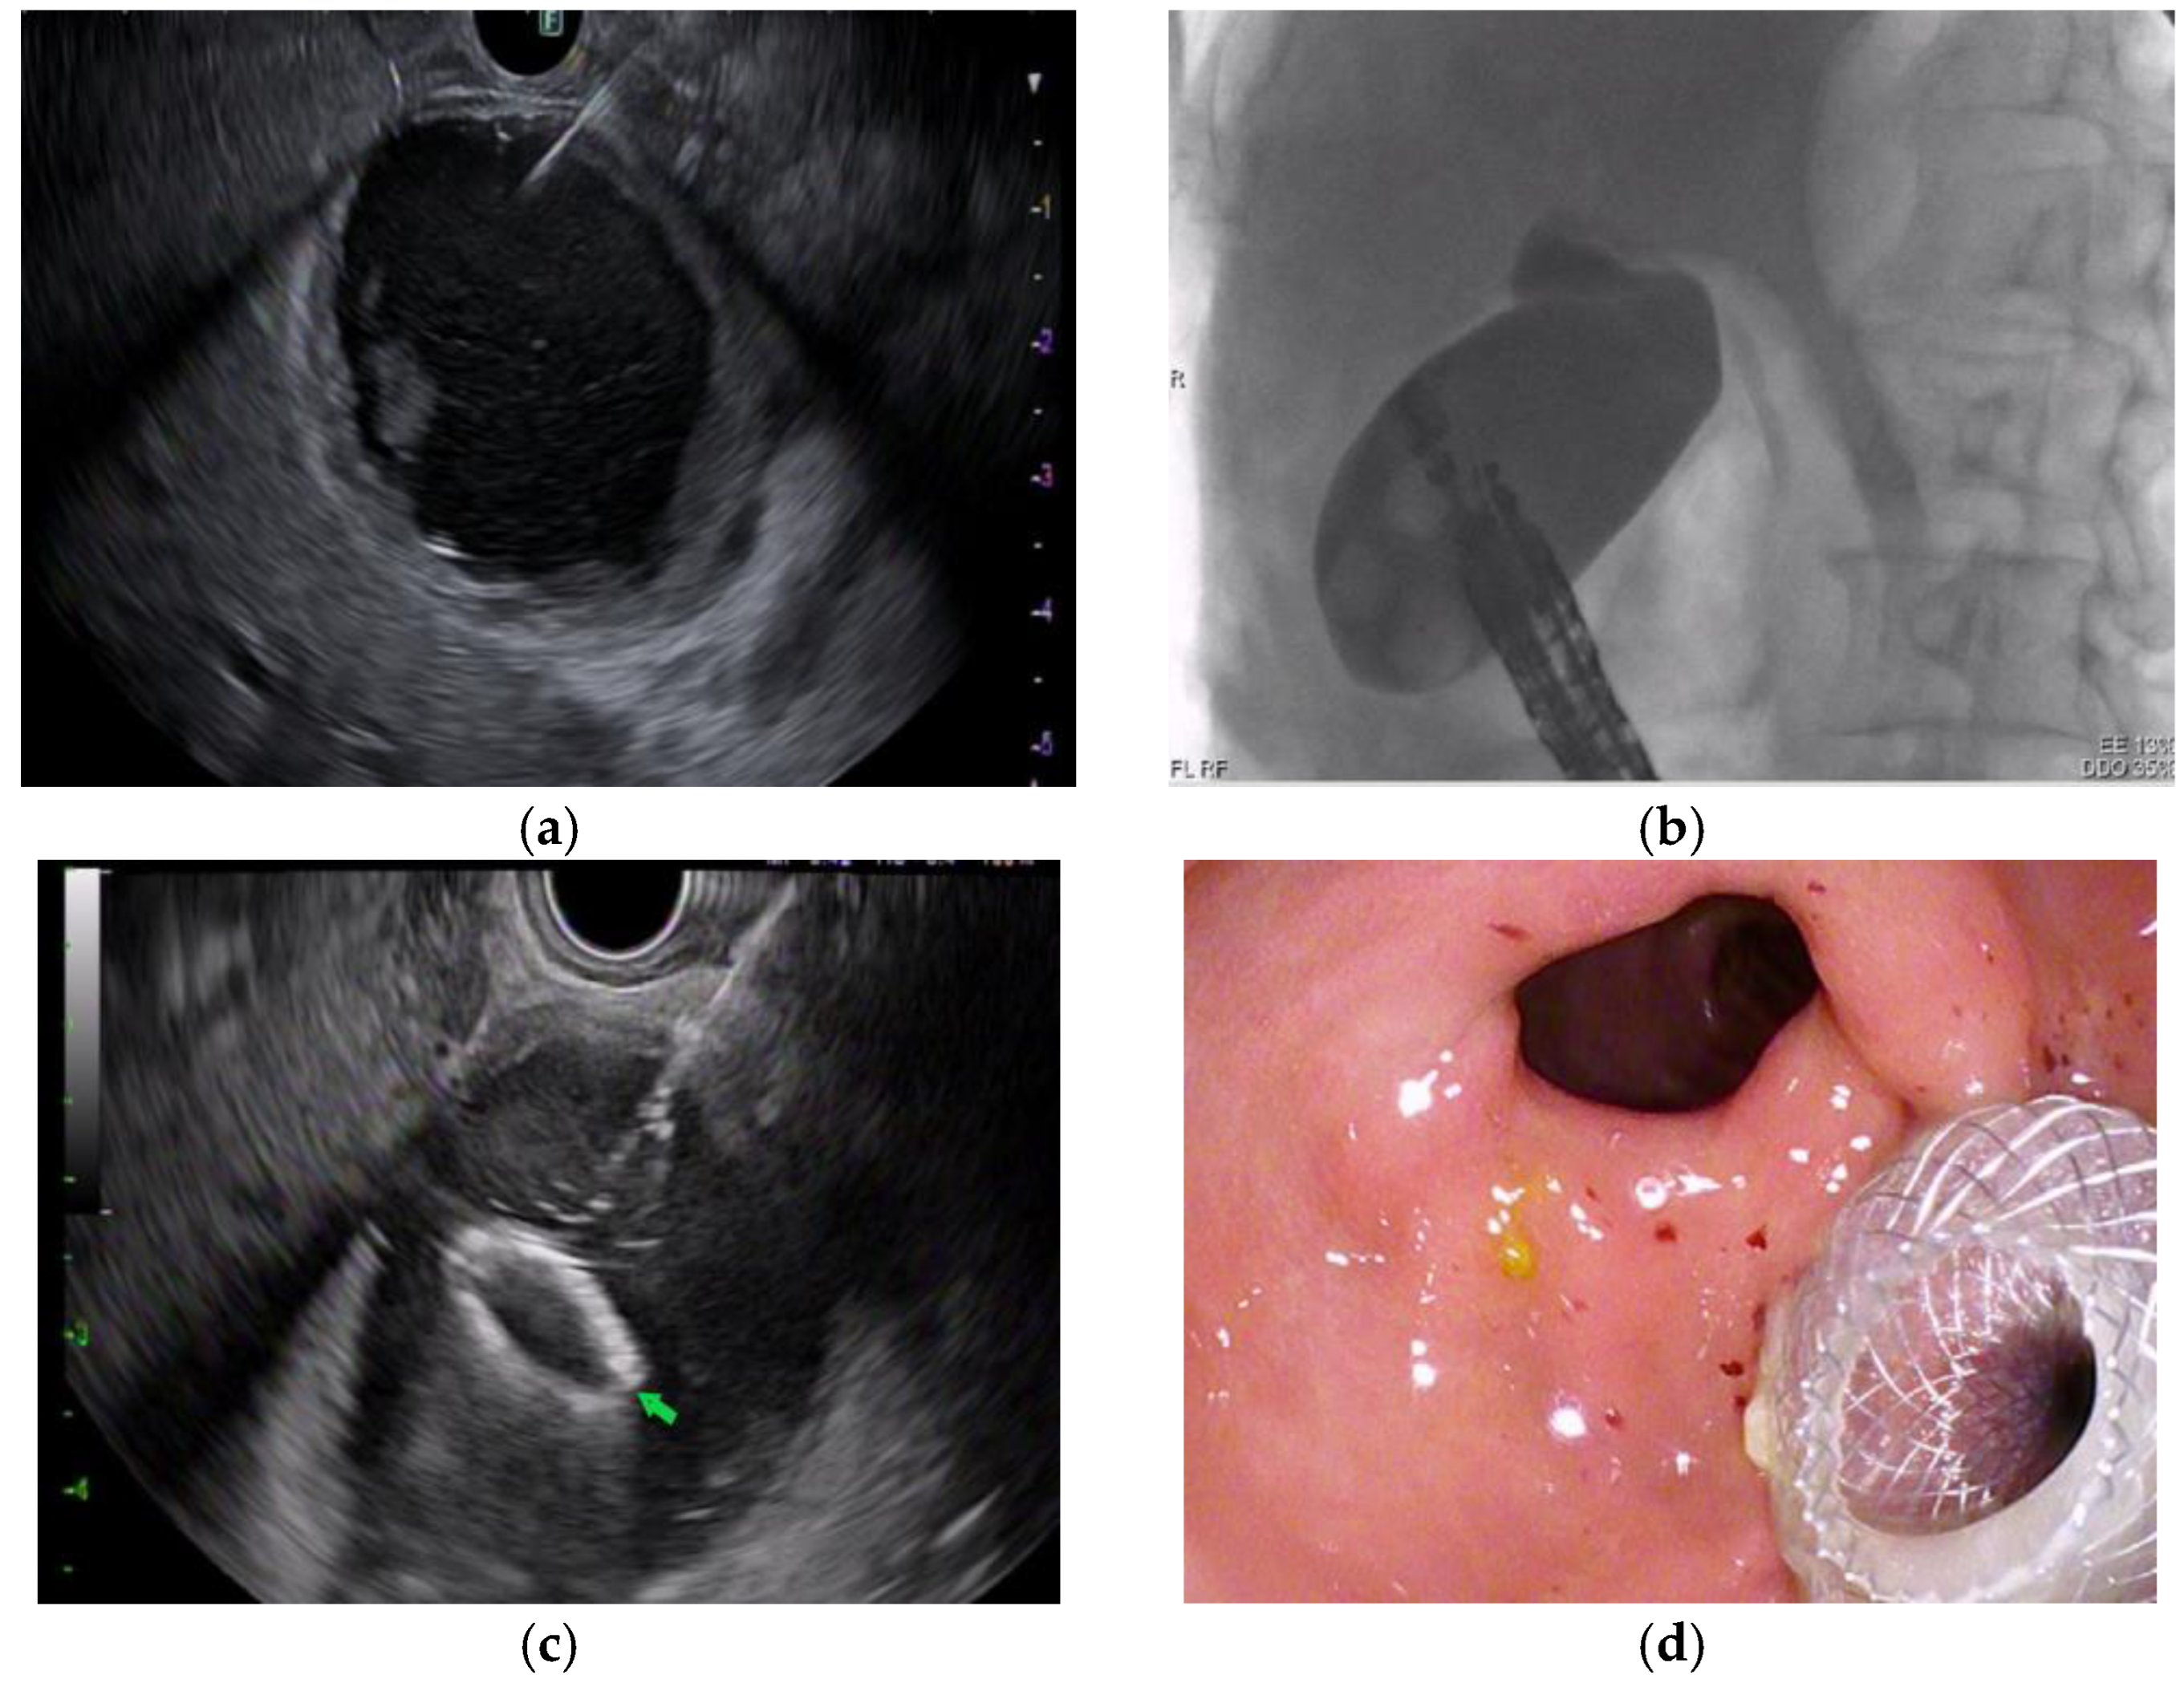

2.4. Procedure Detail